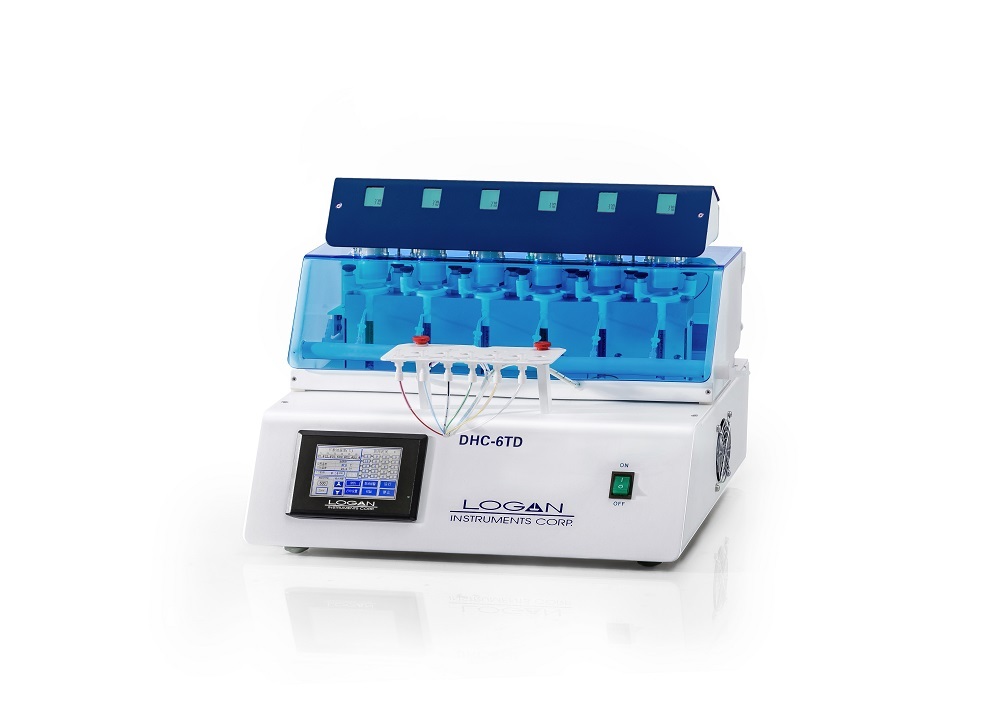

LOGAN Instruments Corp.(以下譯為(wèi)“祿亘”)自1990年成立于美國(guó)新(xīn)澤西州,如···